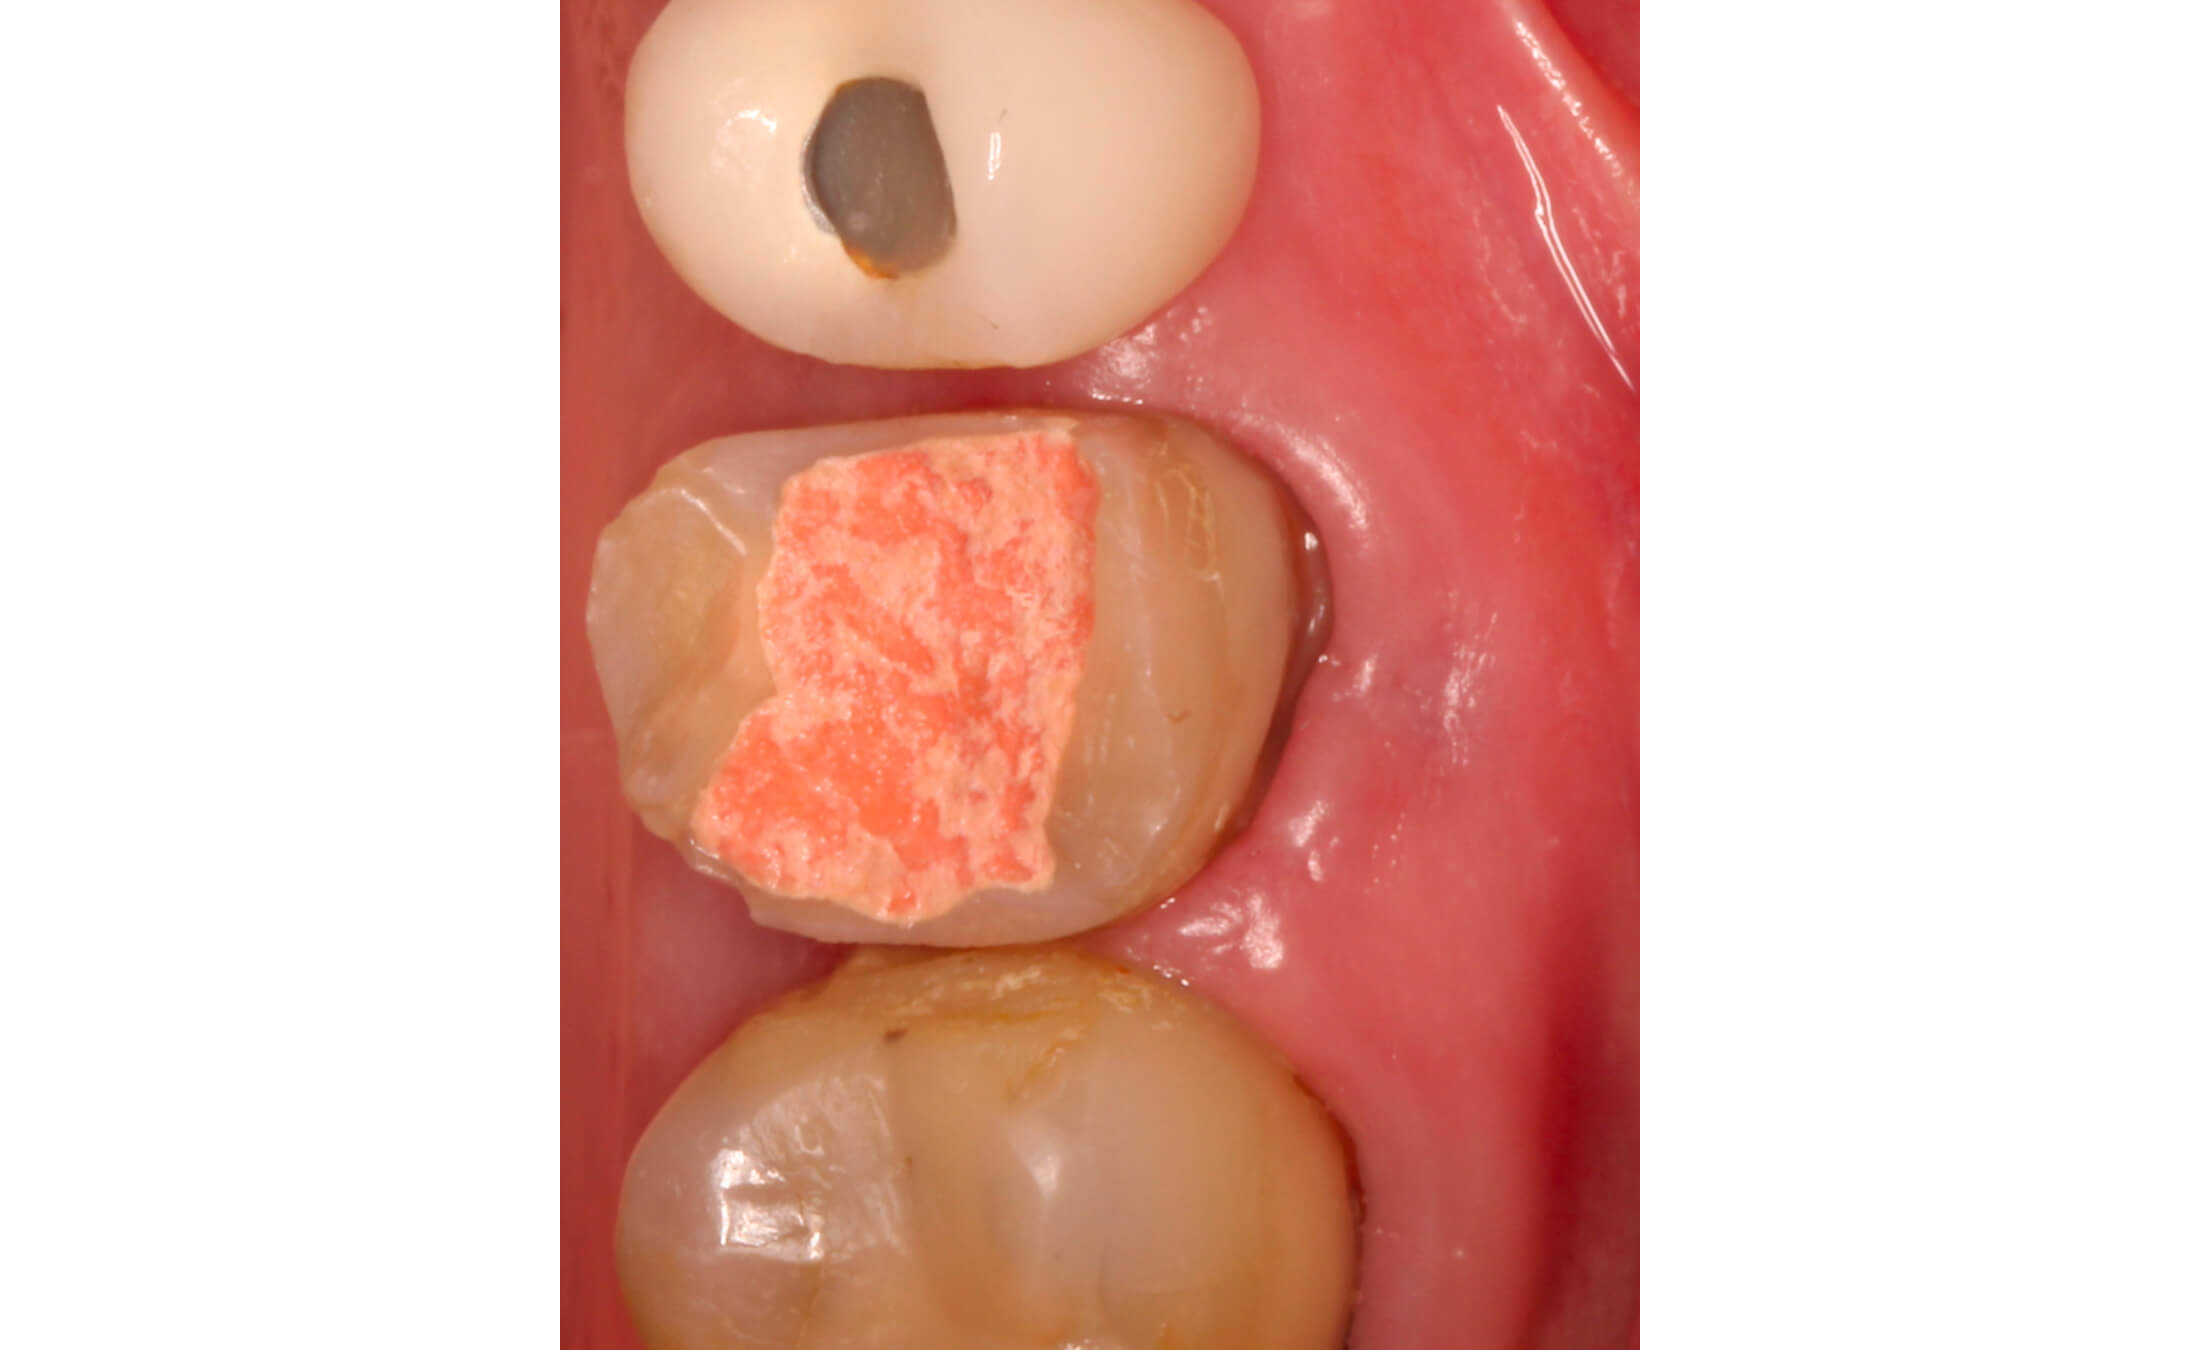

2. В первое посещение выполнена ревизия, дезобтурация корневых каналов, механическая и медикаментозная обработка, каналы временно обтурированы препаратом на основе гидроксида кальция сроком на 2 недели. (Фото 5)

3. Через две недели свищевой ход закрылся. (Фото 6)